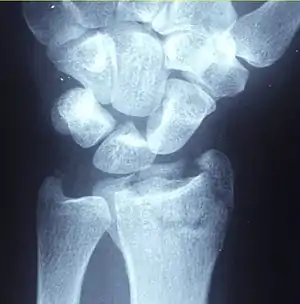

Malreduced distal radius fracture demonstrating the deformity in the wrist

Dorsal displacement of carpal bones seen in dorsally angulated distal radius fracture, creating a fork-like appearance

"Dinner fork" deformity

Swelling, deformity, tenderness, and loss of wrist motion are normal features on examination of a person with a distal radius fracture. "Dinner fork" deformity of the wrist is caused by dorsal displacement of the carpal bones (Colle's fracture). Reverse deformity is seen in volar angulation (Smith's fracture). The wrist may be radially deviated due to shortening of the radius bone.[5] Examination should also rule out a skin wound which might suggest an open fracture, usually at the side.[5] Tenderness at an area with no obvious deformity may still point to underlying fractures. Decreased sensation especially at the tips of the radial three and one half digits ( thumb, index finger, middle finger and radial portion of the ring finger ) can be due to median nerve injury. Swelling and displacement can cause compression on the median nerve which results in acute carpal tunnel syndrome and requires prompt treatment. Very rarely, pressure on the muscle components of the hand or forearm is sufficient to create a compartment syndrome which can manifest as severe pain and sensory deficits in the hand.[5]